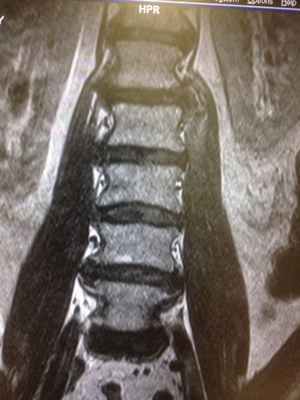

На мр-изображении видно, что большая поясничная мышца находится в состоянии отека, о чем свидетельствует изменение сигнальных характеристик. (гиперинтенсивная, яркая по t2)